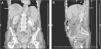

Absceso hepático por Fusobacterium originado en neoplasia ovárica abscesificada

Fusobacterium arising from hepatic abscess and abscessed ovarian neoplasm